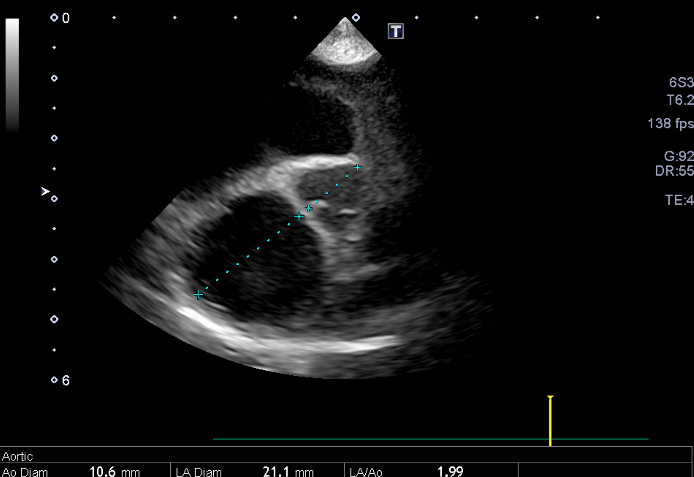

心臓エコー内服開始0日目